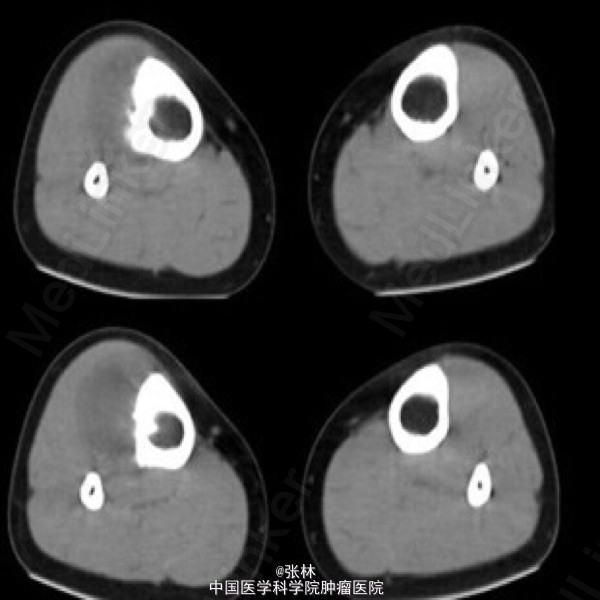

【病史临床】患者,女性,11岁,右侧胫骨上段触痛,血象及皮温不高。

影像表现:右胫骨外侧骨皮质表面低密度软组织肿块,与骨干长轴平行,基底部有条状钙化影,肿块边缘有骨膜新生骨,骨皮质内面未受侵犯,肿块与骨皮质间无透亮间隙。

术后病理结果:尤文氏肉瘤(IIb期)